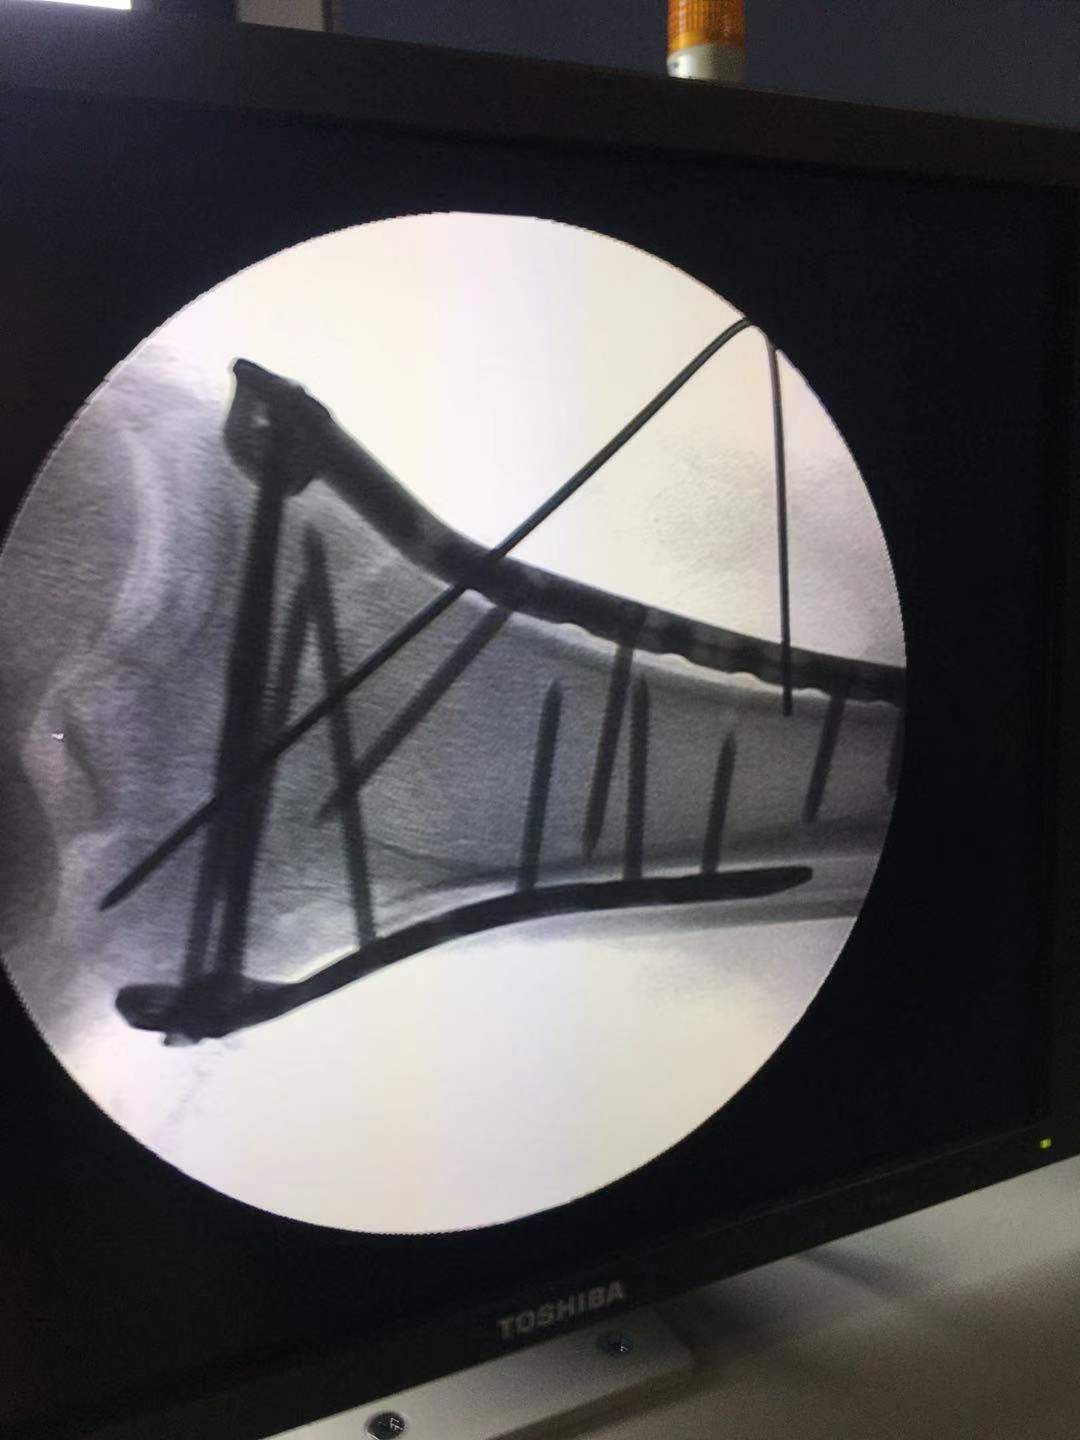

牵引 复位后X光片

透视复位满意后临时固定。

术后复查